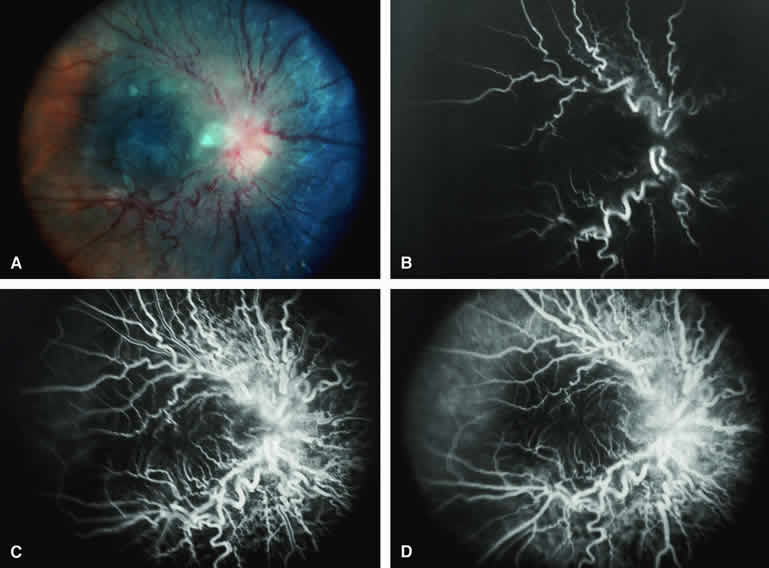

Choroidal Melanoma With Nodular Eruption Through Bruch's Membrane

If a choroidal melanoma has erupted through Bruch's membrane (Figs. 13A and 14A), it forms an apical nodule that is generally hypomelanotic and contains many large-caliber blood vessels. Fluorescein angiography of these tumors (see Fig. 13B, C, and D) typically shows hypofluorescence of the base of the lesion during the early frames, relatively rapid filling of the prominent blood vessels in the apical nodule during the venous and recirculation frames, and intense late staining of the apical nodule resulting from progressive fluorescein leakage by the late-phase frames. Similarly, ICG angiography of these tumors (see Fig. 14B, C, and D) also shows relative early hypofluorescence of the tumor base, early filling of prominent intralesional blood vessels within the apical nodule, intense staining of the apical nodule by the recirculation phase frames, and persistent late hyperfluorescence of the mass.